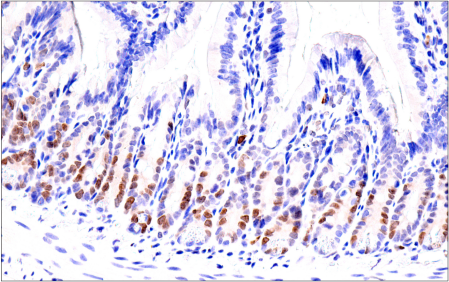

Immunohistochemical analysis of paraffin-embedded normal mouse small intestine using ATAD2 (E8Y7F) Rabbit mAb.

Immunohistochemistry Image 6: ATAD2 (E8Y7F) Rabbit Monoclonal Antibody